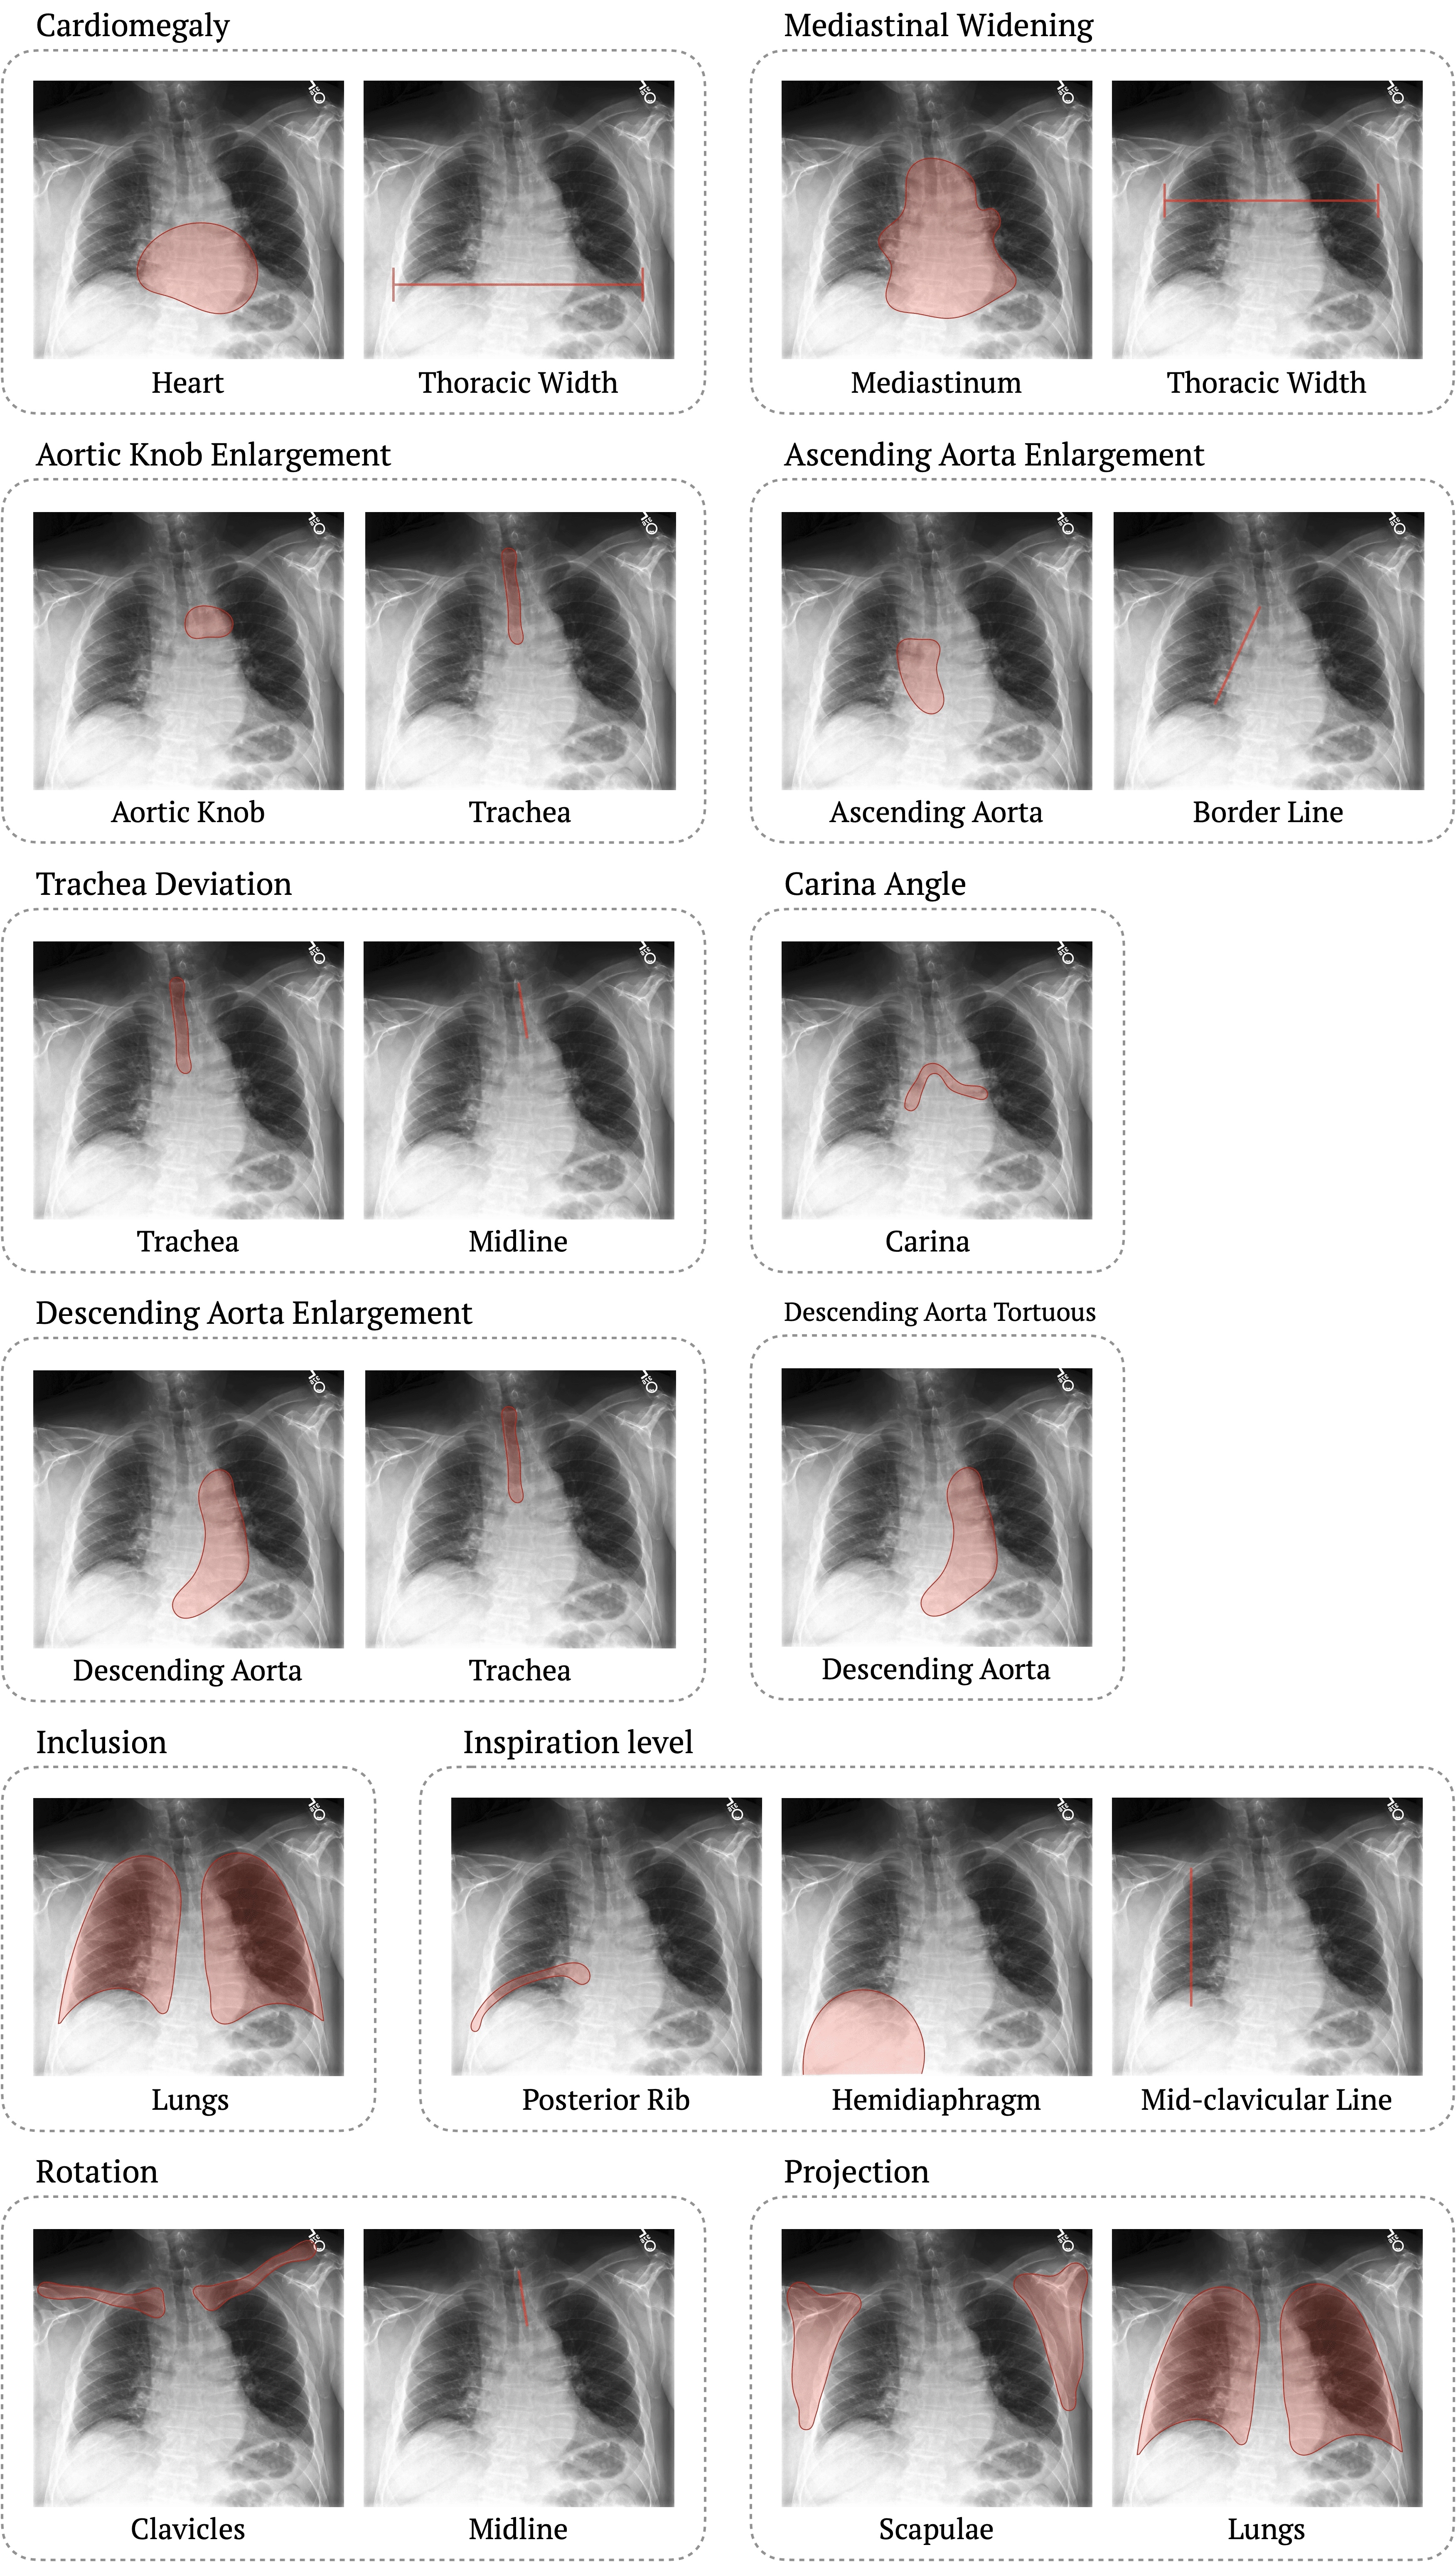

This section presents detailed descriptions of each diagnostic task’s criteria and how corresponding clinical attributes are extracted. For each task, we define clinically grounded measurement criteria and illustrate the extraction process using visual examples based on segmentation masks and anatomical landmarks. These examples demonstrate how quantitative criteria are applied to derive consistent diagnostic evaluation across images.

• Cardiomegaly refers to an enlarged heart silhouette on chest X-rays. It is diagnosed by calculating the cardiothoracic ratio (CTR), defined as the maximal horizontal cardiac diameter divided by the maximal horizontal thoracic diameter. In the PA view, a CTR exceeding 0.50 indicates cardiomegaly. See Figure 4.

• Carina Angle represents the angle formed at the bifurcation of the trachea into the right and left main bronchi. It is measured directly at the point of bifurcation, typically ranging between 40-80 degrees, although normal values may vary slightly across literature. See Figure 5.

• Trachea Deviation refers to the lateral displacement of the trachea from the midline on a chest X-ray. It is assessed by determining whether the trachea lies along the midline defined by the spinous processes or is deviated from it. See Figure 6.

• Inclusion describes whether all relevant thoracic anatomy is fully captured in the image. Proper inclusion is confirmed when the image shows the lung apices, inner margins of the lateral ribs, and costophrenic angles. See Figure 7.

• Rotation refers to the misalignment of the patient during image acquisition. It is evaluated by checking the symmetry of the clavicles relative to the spinous processes. The spinous processes should be equidistant from the medial ends of both clavicles; any asymmetry indicates patient rotation. See Figure 8.

• Mediastinal Widening refers to abnormal broadening of the mediastinum. Traditionally defined as a mediastinal width >8 cm at the aortic arch level on PA chest X-rays, this absolute measurement is not feasible in image-only settings. Instead, we assess the ratio of mediastinal width to thoracic width at the same level, providing a consistent and image-based standard. See Figure 9.

• Aortic Knob Enlargement refers to the prominence of the aortic arch along the left mediastinal border. Traditionally, it has been assessed through visual estimation, which is susceptible to inter-observer variability. We instead quantify it as the ratio between the maximum width of the aortic knob and the median width of the trachea. The trachea is chosen as a reference due to its stable anatomy, ensuring reproducible assessment. See Figure 10.

• Ascending Aorta Enlargement indicates abnormal dilation of the ascending aorta, visible along the right mediastinal border. Conventional evaluation relied on subjective visual inspection, which lacked standardized criteria. We define enlargement based on whether the aorta extends beyond an imaginary line connecting the right heart border and the inner margin of the right lung, providing a consistent and interpretable rule. See Figure 11.

• Descending Aorta Enlargement denotes widening of the descending thoracic aorta, often seen as a prominent left paraspinal contour. Visual estimation was the conventional approach, but it often led to inconsistency. We introduce a ratio-based measurement between the aorta’s maximum width and the median tracheal width, offering a consistent evaluation. See Figure 12.

• Descending Aorta Tortuous describes excessive curvature of the descending thoracic aorta. It was previously evaluated by subjective visual impression, leading to variability. To overcome this, we quantify tortuosity by dividing the aorta into five equal-length sections and annotating six coordinates. Curvature at each point is computed using finite difference methods (central, forward, and backward difference), enabling objective and reproducible evaluation. See Figure 13.

• Inspiration Level assesses the degree of lung expansion during image acquisition, as observed on a chest X-ray. Adequate inspiration is typically indicated by the visualization of 9–10 posterior ribs above the diaphragm. It is measured by counting the number of right posterior ribs intersecting the right hemidiaphragm along the mid-clavicular line. Originally, this criterion lacked a clearly defined reference line, which led to inconsistency in rib counts and variability across evaluators. By introducing the mid-clavicular line as a standardized landmark, we ensure more consistent and reproducible assessment. See Figure 14.

• Projection refers to the orientation of the X-ray beam relative to the patient, typically posteroanterior (PA) or anteroposterior (AP) on chest X-rays. Originally, projection was assessed by visually inspecting scapular positioning, whether the scapulae were retracted (suggesting PA) or overlapping the lung fields (suggesting AP). However, this method lacked clear, objective criteria, leading to variability across evaluators. To address this, we compute the ratio of the overlapping area between each scapula and the lung field to the scapular area. A higher overlap ratio indicates an AP view. This quantitative method provides a standardized and reproducible approach to classification. See Figure 15.

Figure 3 and Table 5 present the subset of anatomical structures segmented by CXAS that were used in CheXStruct for each diagnostic task.

Figure 3: Visualization of the anatomical structures of CXAS used in CheXStruct.